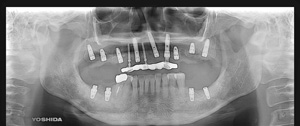

@@R.S‚³‚ñ@56Î —«  ‘åŠw‹³Žö @Žèp“ú@‚Q‚O‚O‚W”N ‚QŒŽ ‚X“úi“yj@㉺Š{  ƒm[ƒxƒ‹ƒKƒCƒhŽg—p@Ö¬“à’ÁÖ@•¹—p@@@

@@@@@ãŠ{  All on ‚U@‘¦Žž‰Ád@@

@@@@@@@@@@@@@ Rpl Tapered Rp  ‚P‚O mm(‚U–{)

@@@@@‰ºŠ{¶‰E@‘¦Žž‰Ád@ ‚R Unit Bridge@

@@@@@@@@@@@ @Rpl Tapered Rp  ‚P‚O mm(‚S–{)@@–ƒWƒ‹ƒRƒjƒAƒNƒ‰ƒEƒ“‚ÅÅI•â’Ô